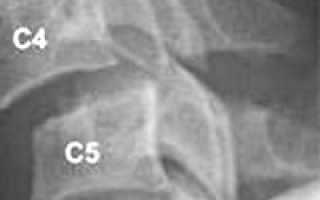

Рентгенологическое исследование является основным методом диагностики. Шейный отдел позвоночника исследуется в пяти проекциях:

• переднезадняя проекция;

• боковая;

• снимки в боковой проекции со сгибанием и разгибанием головы;

• прямой снимок через открытый рот.[3]

Этот стандарт исследования минимизирует возможность ошибок диагностики, так как подвывих иногда выявляется только на функциональных снимках. Исследование шейного отдела позвоночника в двух или трех стандартных проекциях не дает достаточной информации, чтобы диагностировать подвывих атланта, который часто остается нераспознанным.[4]

Для исследования грудного и поясничного отдела используются переднезадняя и боковая проекции, включая снимок со сгибанием и разгибанием. В ряде случаев дополнительно проводится МРТ или КТ позвоночника, при осложнениях — электромиография и ультразвуковое исследование сосудов головного мозга.[12]